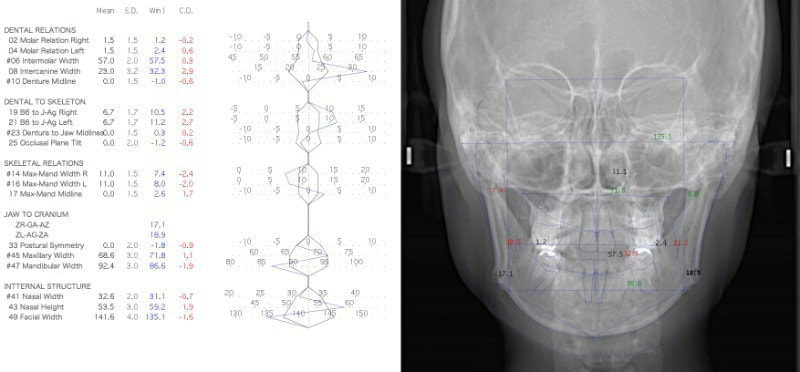

検査時セファロ分析

検査時セファロ分析正貌